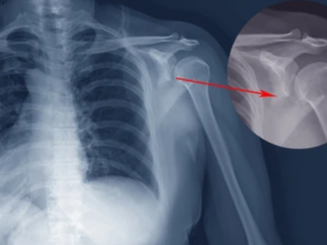

Q5. 골절 후 뼈가 잘 붙고 있는지 확인하는 방법은 무엇인가요?

A5. 가장 일반적인 방법은 정기적인 X-ray 촬영입니다. 회복 기간 동안 2~4주 간격으로 촬영하며, 뼈가 서서히 이어지는 골유합 상태를 확인합니다. 뼈가 제대로 유합되고 있다면 점점 뿌옇고 두꺼운 ‘골막’이 보이게 되고, 통증도 서서히 줄어듭니다. 간혹 유합이 잘 되지 않으면 초음파나 CT 검사를 병행하기도 합니다.